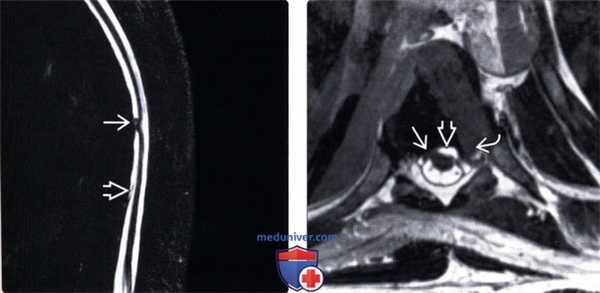

(Слева) На Т2 МР-миелограмме отмечается фокальная деформация и изгиб грудного отдела спинного мозга. Обратите внимание на смещение края дурального мешка, свидетельствующее об экстрадуральном накоплении контраста, связанном с наличием дефекта твердой мозговой оболочки.

(Справа) На Т2 CISS МР-И определяется пролаби-рование спинного мозга через дефект твердой мозговой оболочки, а также экстрадуральное скопление жидкости вдоль вентральной поверхности дурального мешка. Обратите внимание на наличие также грыжи межпозвонкового диска.